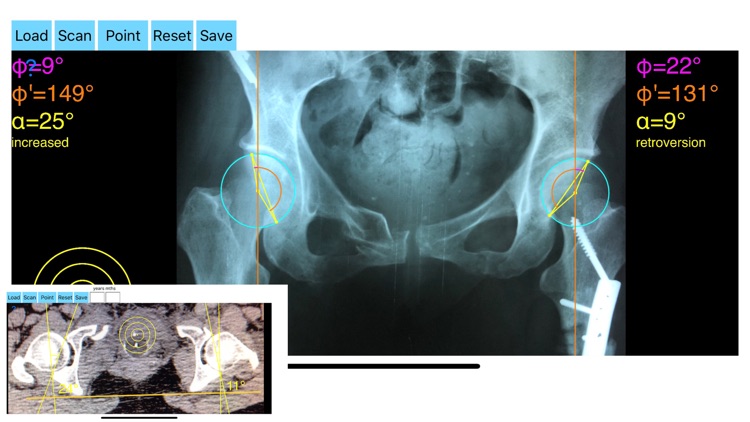

AcetabularAnteversionApp screenshot-0

Acetabular version is conventionally evaluated on CT scans but excessive radiation doses associated with routine use of computed tomography (CT). An objective radiographic tool which provides measurements comparable in accuracy to CT measurements has been developed by Dr. Hefti (Nomogram).Tedious and time-consuming calculation has to be done in simple X-rays in order to calculate the acetabular anteversion. The primary goal of this App is to help determine radiographic values of acetabular anteversion in a practice in a blink of an eye and avoiding CT scans.

-By marking certain points in a simple standard AP pelvic radiograph, geometric parameters are being calculated. The App computes the acetabular anteversion based on a pelvic AP radiograph. The angle of anteversion is calculated through the formula according to Heftis nomogram. The acetabular orientation (anteversion/retroversion) is determine by the app by the measurement of the angles between the center of the femoral head and the anterior (φ) and posterior (φ’) acetabular rim.

Once you choose correctly the anterior and posterior acetabular rims the app calculates the acetabular anteversion based on nomogram.

-The data are printed over to screen so each case can easily assessed